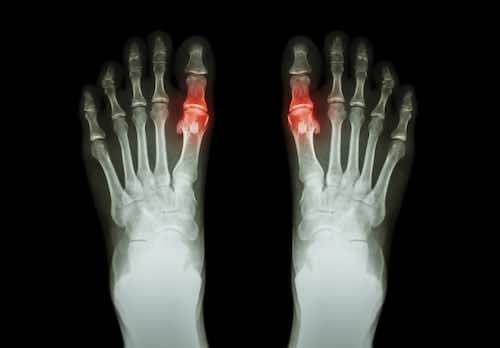

Krystaly kyseliny močové se usazují zejména v kloubech a šlachách, ale mohou se ukládat i ve vnitřních orgánech, především v ledvinách. V těchto místech mohou uvíznout a svým ostrým hrotem se zabodávat, čímž způsobují řadu komplikací.

- Intenzivní bolest kloubů: Dna se projevuje především silnou bolestí některých kloubů, ke které dochází nejčastěji v noci a brzy ráno. Postižen bývá hlavně palec u nohy, ale dna může zasáhnout i klouby rukou, kotníků a kolenou.

- Zarudnutí a otok kloubů: Oblast v okolí postižených kloubů bývá zarudlá, oteklá a citlivá na dotek. Kůže na kloubu je lesklá a napnutá.

- Omezená pohyblivost: Neléčená dna může vést k deformaci kloubu a zánětu, což má za následek potíže s hybností.